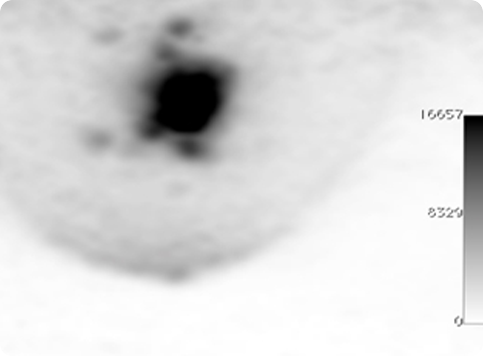

PETsys has developed two PET prototypes based on APD-based detector modules which target breast cancer applications (Clear PEM System).

These systems comprise 12288 APD's and 6144 scintillation crystals, organized into two opposing detector plates. One of these is located at ICNAS in Coimbra (PT) - (Fig. 5).

Due to its very good spatial resolution and accessibility of the Field-of-View, the Clear-PEM system can also be used for small animal imaging.